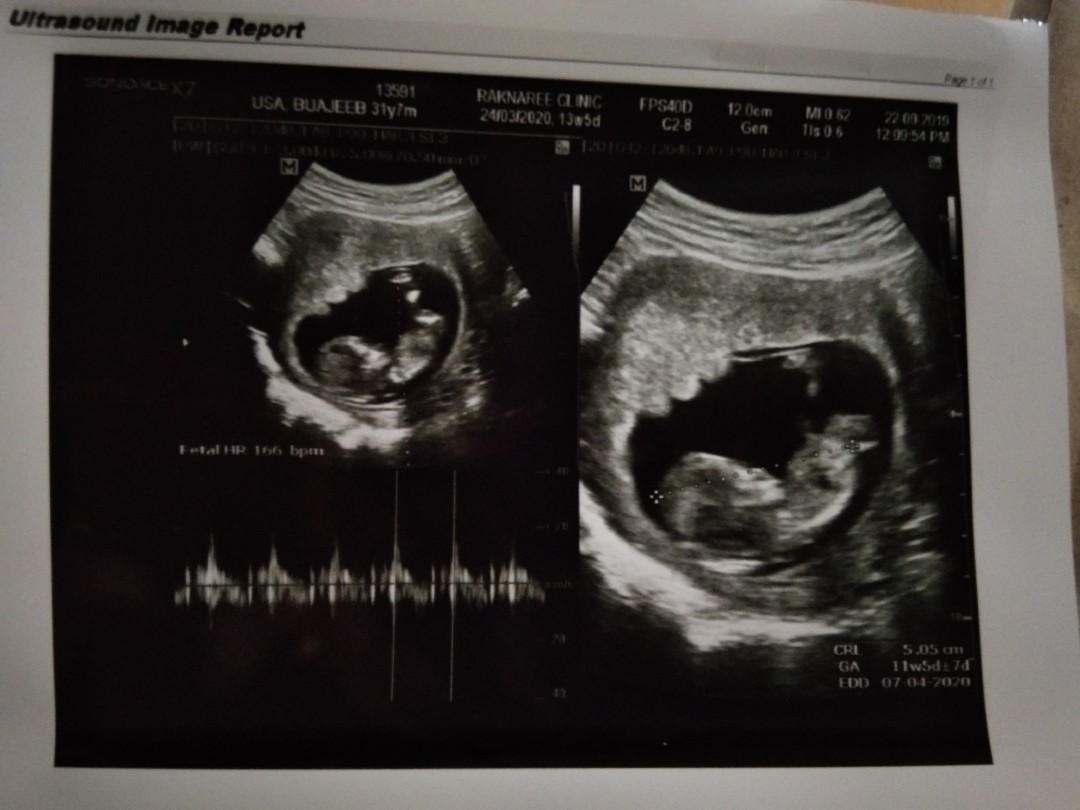

12 week ka

12 วีค4วันจ้า

12วีคค่ะ💕

ตอน12wค่ะ

12วีคค่ะ

12w2d จ้า